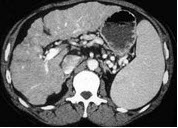

男,71岁,继往有肝炎病史,CT检查如图,请选择最佳诊断( )

A:脂肪肝

B:肝癌

C:肝硬化

D:肝转移瘤

E:肝色素沉着症